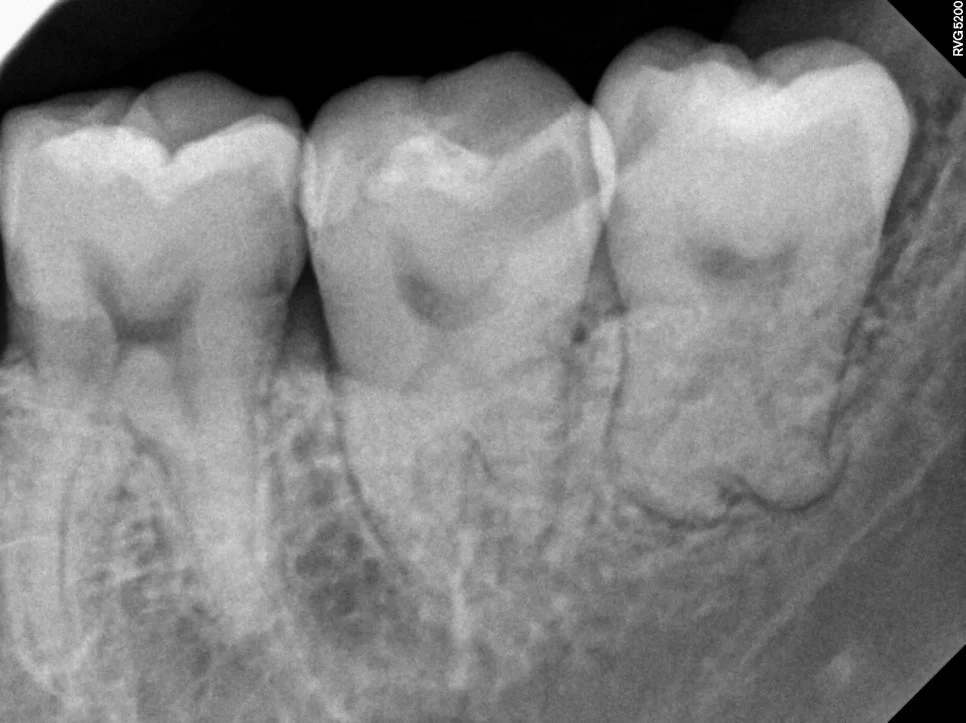

좌측 매복 사랑니 진단

매복 사랑니 좌측 치근단 X-ray

좌측 치근단 X-ray

제2대구치와 사이 관리가 어려운 좌측 하악 매복 사랑니입니다. 살짝 맹출된 상태이지만 관리가 되지 않아 발치가 필요한 상태입니다.